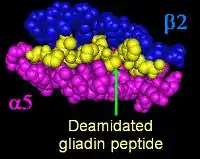

Most people with coeliac bear a two-gene HLA-DQ2 haplotype referred to as DQ2.5 haplotype. This haplotype is composed of two adjacent gene alleles, DQA1*0501 and DQB1*0201, which encode the two subunits, DQ α5 and DQ β2. In most individuals, this DQ2.5 isoform is encoded by one of two chromosomes 6 inherited from parents (DQ2.5cis). Most coeliacs inherit only one copy of this DQ2.5 haplotype, while some inherit it from both parents; the latter are especially at risk for coeliac disease as well as being more susceptible to severe complications.[64]

Some individuals inherit DQ2.5 from one parent and an additional portion of the haplotype (either DQB1*02 or DQA1*05) from the other parent, increasing risk. Less commonly, some individuals inherit the DQA1*05 allele from one parent and the DQB1*02 from the other parent (DQ2.5trans) (called a trans-haplotype association), and these individuals are at similar risk for coeliac disease as those with a single DQ2.5-bearing chromosome 6, but in this instance, the disease tends not to be familial. Among the 6% of European coeliacs that do not have DQ2.5 (cis or trans) or DQ8 (encoded by the haplotype DQA1*03:DQB1*0302), 4% have the DQ2.2 isoform, and the remaining 2% lack DQ2 or DQ8.[65]

Membrane leaking permits peptides of gliadin that stimulate two levels of the immune response: the innate response, and the adaptive (T-helper cell-mediated) response. One protease-resistant peptide from α-gliadin contains a region that stimulates lymphocytes and results in the release of interleukin-15. This innate response to gliadin results in immune-system signalling that attracts inflammatory cells and increases the release of inflammatory chemicals.[28] The strongest and most common adaptive response to gliadin is directed toward an α2-gliadin fragment of 33 amino acids in length.[28]

The response to the 33mer occurs in most coeliacs who have a DQ2 isoform. This peptide, when altered by intestinal transglutaminase, has a high density of overlapping T-cell epitopes. This increases the likelihood that the DQ2 isoform will bind, and stay bound to, peptide when recognised by T-cells.[75] Gliadin in wheat is the best-understood member of this family, but other prolamins exist, and hordein (from barley), secalin (from rye), and avenin (from oats) may contribute to coeliac disease.[28][49][76] Avenin's toxicity in people with coeliac disease depends on the oat cultivar consumed, as prolamin genes, protein amino acid sequences, and the immunoreactivities of toxic prolamins vary among oat varieties.[20]